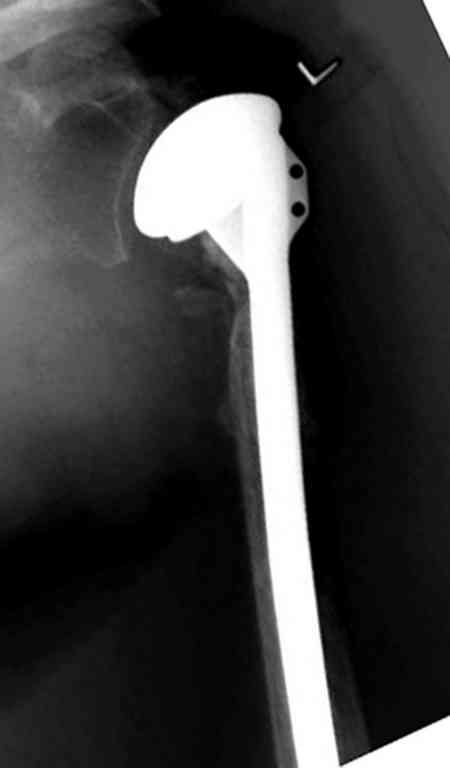

По Neer операцию рекомендовали только тогда, когда угол между диафизом и головкой составляет около 45 градусов, и переломы с меньшим углом смещения считали благоприятным для функционального результата.

Хотя "варусная импакция" в проксимальном отделе плеча срастается хорошо консервативными мерами, но в результате при восстановлении такие больные теряют часть отведения, и тем более у больной варус осложнен еще сгибанием.

Закрытые репозиции без фиксации из-за вторичного смещения неэффективны, поэтому рекомендуется репозиция с фиксацией. Методик много, кто чем владеет и отдает предпочтение закрытые-открытые, перкутанные, с блокирующими пластинами, гвоздь, множественными спицами или методом спиц по Лазареву, и осторожно с манипуляциями из=за возможности повреждения аксиллярного нерва - частый вид осложнении.

Неправильно выбранная тактика по фиксации или технические ошибки во время операции могут привести к серьезным осложнениям. Здесь привожу

пример из нашей практики, вроде обычный перелом шейки, фиксированный популярным методом "Сиэтла" - множественными спицами 2.8 мм с резьбой на конце.

При первичном осмотре в поликлинике через 3 недели обнаружили миграцию двух спиц, срочно госпитализированному на второй день перед операцией на всякий случай сделали снимок, одна спица находилась под ключицей в шейном отделе (на снимке).